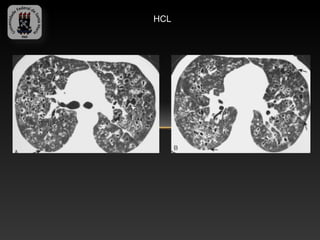

-HISTIOCITOSE DE CELS DE LANGERHANS

-Patologia de adultos jovens fumantes de 30 – 40 anos.

-Caracterizada pelo acúmulo de cels de Langerhans na superfície epitelial

do trato respiratório.

-Achados TC:

-   Micronodulos centrolobulares

-   Cistos lisos que coalescem e formam espaços aéreos bizarros

-   Predominam nas regiões superiores e geralmente os seios

costofrênicos são poupados.

HCL